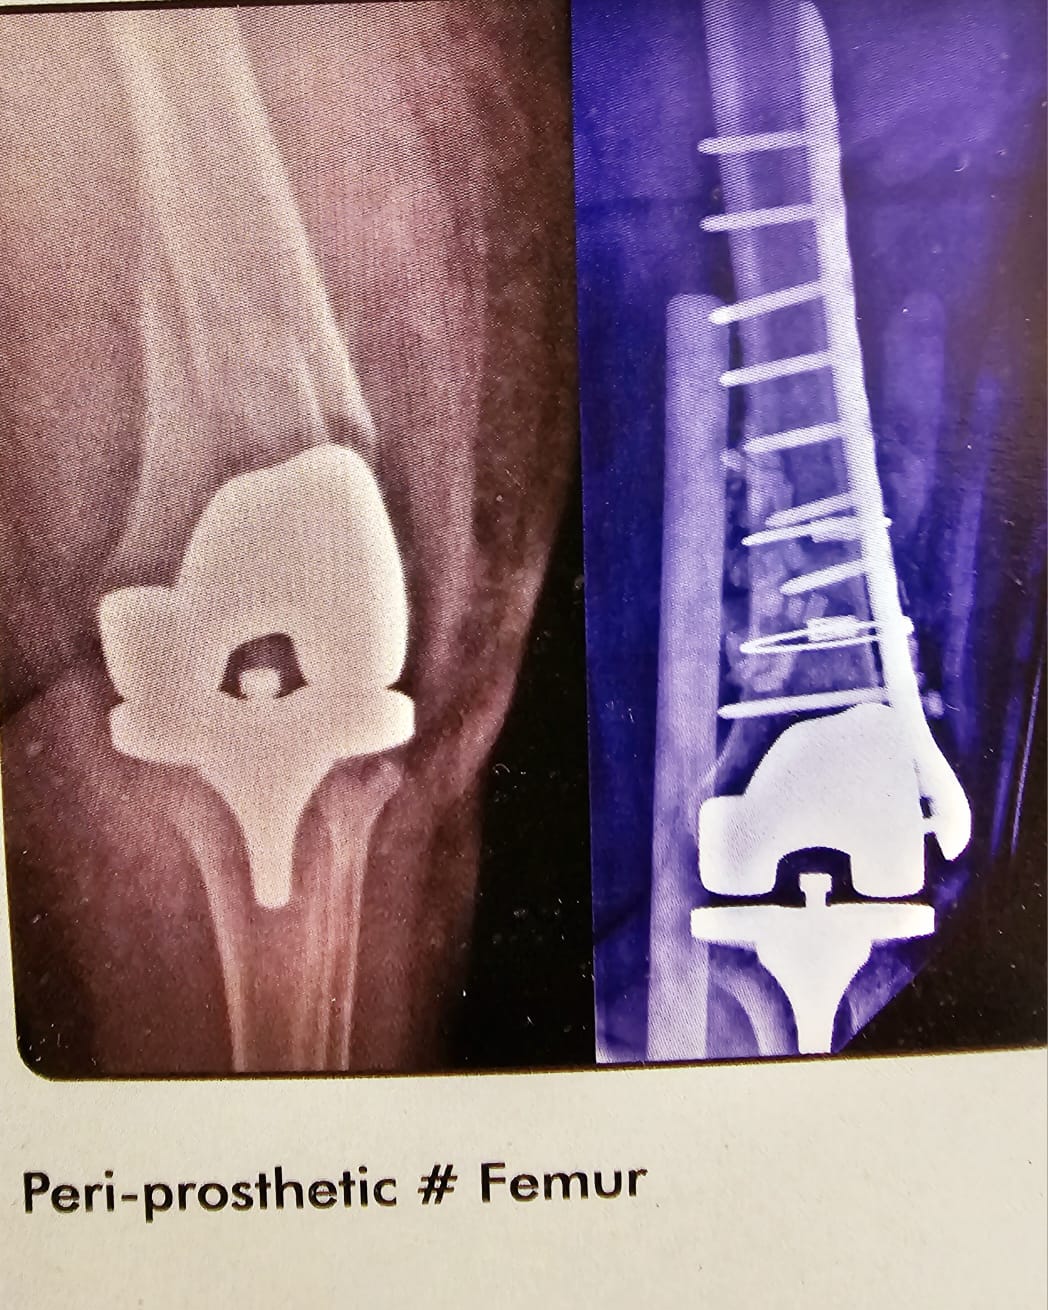

Peri prosthetic # Femur

This lady came all the way from Tanzania, She had a fracture of the shaft of Femur. Just above the total knee which was done 5 years earlier. The tibial component and the femural component were stable. There was no loosening. I did a Contera plate and with bone graft and circulage wires. And she did well.